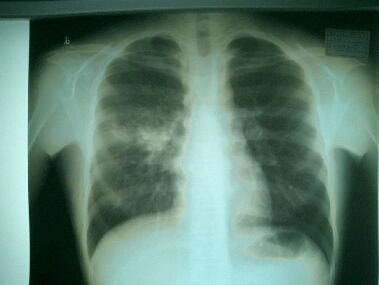

マイコプラズマ肺炎

マイコプラズマ肺炎 を発症すると現れる症状はご存知ですか 医師が監修 メディカルドック

発熱と咳に注意 大人のマイコプラズマ肺炎 健康 医療トピックス オムロン ヘルスケア

子どもや若者に多い マイコプラズマ肺炎 に注意 その症状と治療法 Nhk健康チャンネル